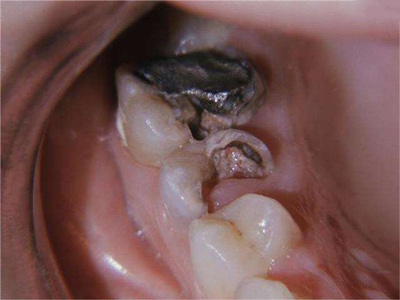

牙齿

缺损

智齿冠周炎大牙发黑缺了一半图

智齿冠周炎患者可出现第二磨牙龋坏变黑,是由于智齿倾斜阻生,与第二磨牙之间形成间隙,间隙不易清洁,食物和细菌积存,长此以往可导致牙齿龋坏发黑甚至出现缺损。